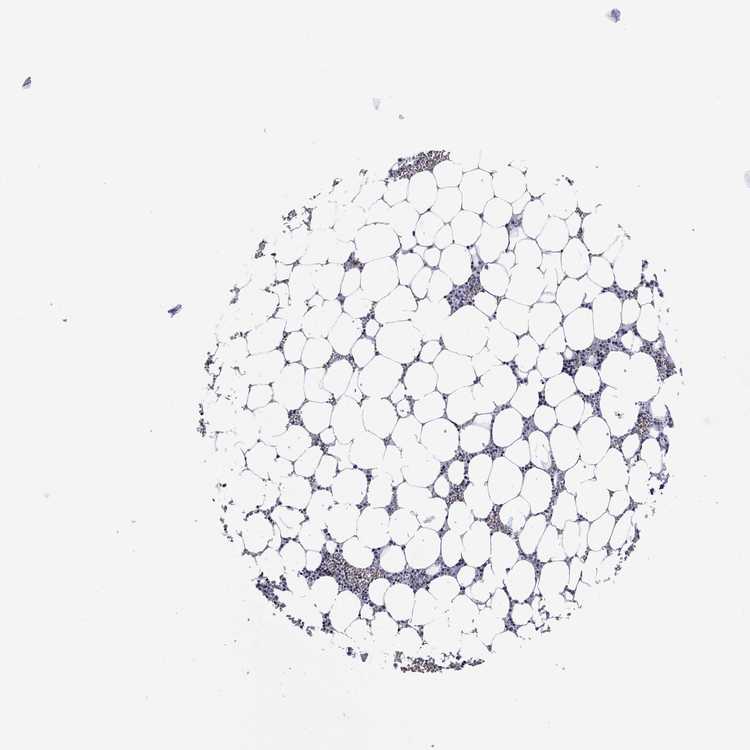

BONE MARROW - Antibody stainingi

Antibody staining in the annotated cell types in the current human tissue is reported as not detected, low, medium, or high, based on conventional immunohistochemistry profiling in selected tissues. This score is based on the combination of the staining intensity and fraction of stained cells.

Each image is clickable and will lead to virtual microscopy that enables deeper exploration of all samples and also displays staining intensity scores, fraction scores and subcellular localization as well as patient and tissue information for each sample.

Antibody HPA074057

Hematopoietic cells Medium